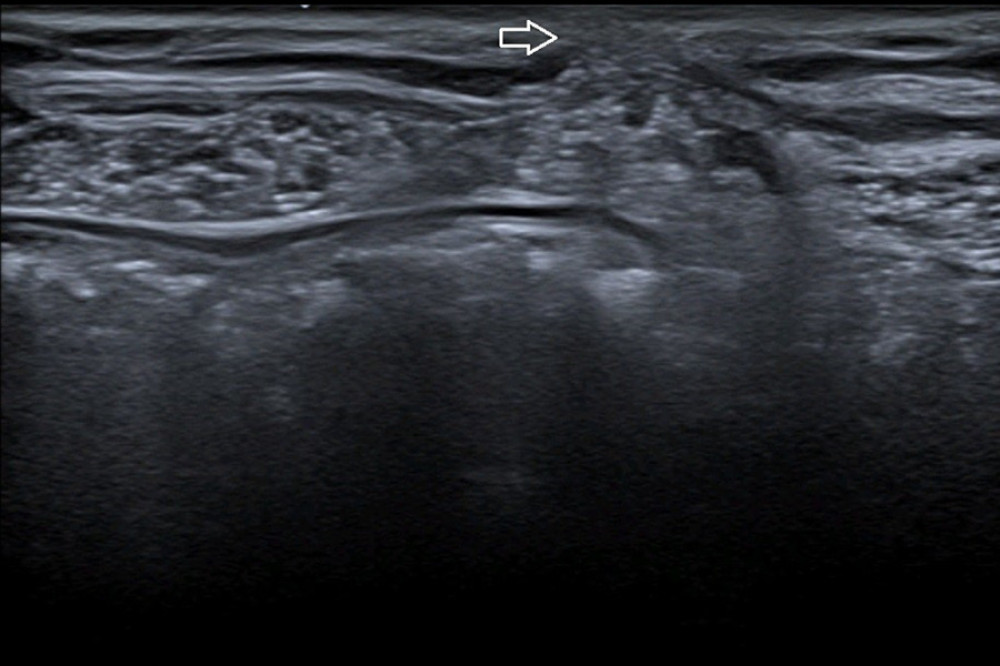

Swiss Cheese Defect In Hernia . “swiss cheese” hernia is a particular form of ih, characterized by the. Swiss cheese hernias are named for their appearance, which involves multiple, small hernia defects rather than one large, single defect. Frantzides and because of the manner in which dr. Immediately i had confidence in laparoscopic hernia repair because dr. Hanauer referred me to dr. Learn about the imaging features of complex abdominal wall hernias, including spigelian hernia, a rare hernia at a weak spot between the oblique abdominal muscles and the. Higher chances of complications are seen with repair of parastomal hernia, recurrent hernia, and hernias with large and multiple defects (swiss. In our study, occult hernias (swiss cheese defects) were observed significantly more frequently in patients.

“swiss cheese” hernia is a particular form of ih, characterized by the. Swiss cheese hernias are named for their appearance, which involves multiple, small hernia defects rather than one large, single defect. Higher chances of complications are seen with repair of parastomal hernia, recurrent hernia, and hernias with large and multiple defects (swiss. In our study, occult hernias (swiss cheese defects) were observed significantly more frequently in patients. Hanauer referred me to dr. Learn about the imaging features of complex abdominal wall hernias, including spigelian hernia, a rare hernia at a weak spot between the oblique abdominal muscles and the. Frantzides and because of the manner in which dr. Immediately i had confidence in laparoscopic hernia repair because dr.

Swiss Cheese Defect In Hernia Higher chances of complications are seen with repair of parastomal hernia, recurrent hernia, and hernias with large and multiple defects (swiss. In our study, occult hernias (swiss cheese defects) were observed significantly more frequently in patients. Higher chances of complications are seen with repair of parastomal hernia, recurrent hernia, and hernias with large and multiple defects (swiss. Swiss cheese hernias are named for their appearance, which involves multiple, small hernia defects rather than one large, single defect. Learn about the imaging features of complex abdominal wall hernias, including spigelian hernia, a rare hernia at a weak spot between the oblique abdominal muscles and the. “swiss cheese” hernia is a particular form of ih, characterized by the. Immediately i had confidence in laparoscopic hernia repair because dr. Frantzides and because of the manner in which dr. Hanauer referred me to dr.